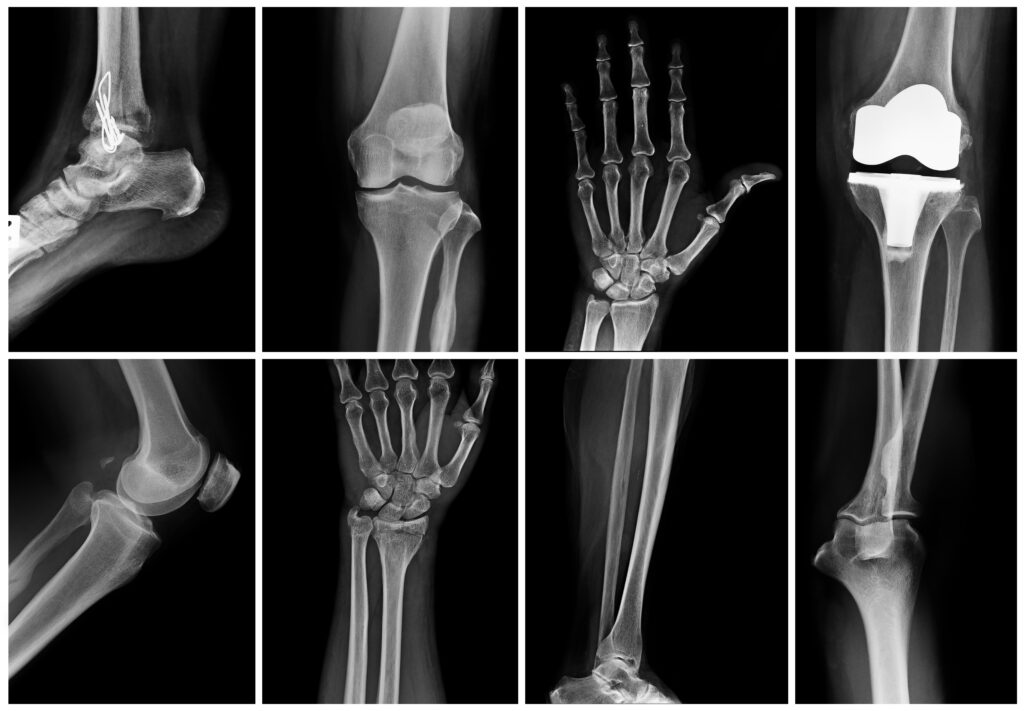

Do You Need an MRI, CT Scan, or X-Ray? How Orthopedic Providers Decide

If you’re dealing with sudden pain, a sports injury, or an issue that’s lingered for weeks, you may be wondering: Do I need imaging—and if so, which kind? MRI, CT scans, and X-rays all play different roles in orthopedic care, and the right choice depends on your symptoms, injury type, and timeline.

Many patients assume advanced imaging like an MRI is required for every orthopedic issue. In reality, most conditions can be evaluated accurately with a thoughtful exam and the appropriate level of imaging. This guide explains the differences between MRI, CT scans, and X-rays—and how orthopedic providers decide which, if any, you need.

X-Rays: The First Step for Most Injuries

X-rays are often the starting point in orthopedic care. They’re quick, widely available, and excellent for evaluating:

If you’ve had a fall, sudden injury, or acute pain, an X-ray is usually the first imaging tool used. In many cases, it provides all the information needed to move forward with treatment.